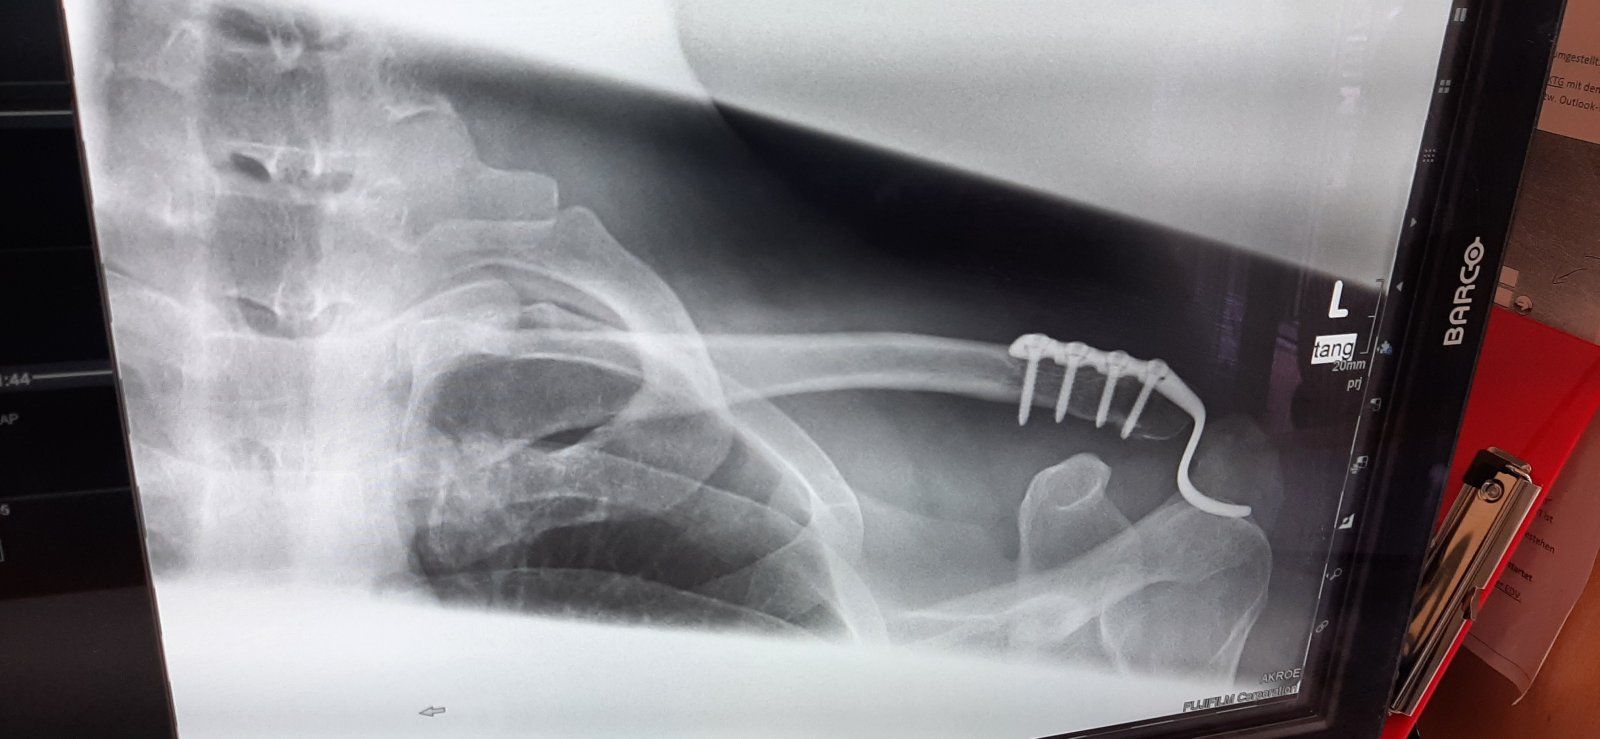

Eine normale Platte wäre kein problem..Hoffe das die mitte kommenden Monat raus kann.

Ich darf den Arm ja nur nicht höher als 90° bewegen, ansonsten bin ich auch schon seit dem Unfall komplett schmerzfrei. Die gebrochen Rippen diagonal gegenüber von der Schulter stören da schon mehr. Ich kann weder auf der rechten noch auf der linken Seite schlafen, welch eine Strafe.